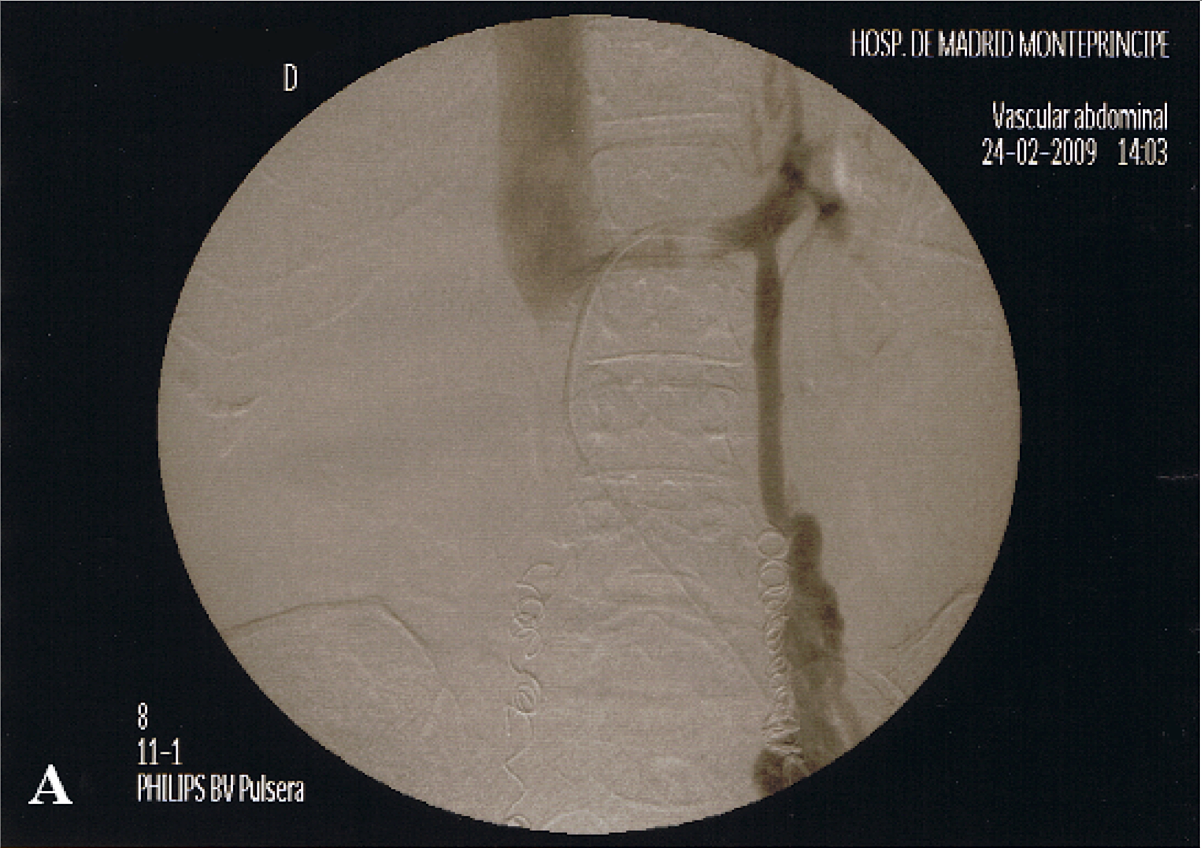

Complications Of Embolization - Dadun: Página De Inicio

For each of the possible complications of embolization. What follows is a description of the complications that can arise when different vascular areas are embolized. Embolization with particles or liquid agents may be performed, most commonly preoperatively with the ... Access Document